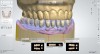

Fig 5. The digital impression was exported from the intraoral scanner and imported into a dental laboratory software package, and using a wizard step-by-step function, the prosthesis scan was converted into a digital denture with two files: one for the teeth arch and the second for the denture base.

Figure 5